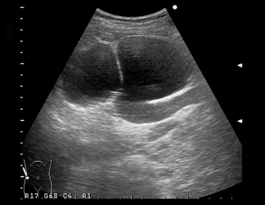

場合によっては、別の病気の検査中に馬蹄形腎臓があることが判明する人もいます。これには、超音波スキャンまたはMRI スキャンが含まれる場合があります。

• 超音波スキャン

超音波

医療専門家は、超音波を使用して腎臓の腫瘤を観察することもできます。このタイプのイメージングでは、塊が固体か液体で満たされているか、あるいは空気を含んでいるかを示すことができます。腎臓の腫瘤の超音波画像では、良性腫瘍と転移した癌の違いを示すこともあります。